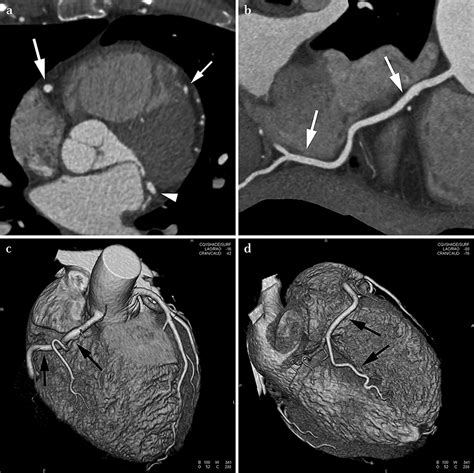

At its core, a Cardiac CT scan is an imaging test that allows cardiologists and radiologists to see if your coronary arteries are narrowed or blocked by plaque buildup—a condition known as atherosclerosis. Unlike traditional stress tests, which provide functional information about how your heart handles exertion, a cardiac CT provides anatomical information. It captures images of the heart while it is beating, using sophisticated gating technology to synchronize the image acquisition with your heart rhythm.

This technology is particularly effective at identifying early-stage heart disease before symptoms manifest. By visualizing the calcified and non-calcified plaque within the arterial walls, physicians can initiate preventative treatments far earlier than previously possible.

Once the scan is complete, the images are sent to a radiologist or a specialized cardiologist who analyzes the anatomy of your coronary arteries. They will look for the presence and extent of plaque, the degree of arterial narrowing (stenosis), and the presence of any calcium deposits. You will receive a formal report, and your primary doctor will discuss the findings with you to determine the next steps in your care plan. Depending on the findings, these steps may include lifestyle modifications, cholesterol-lowering medication, or further diagnostic testing.